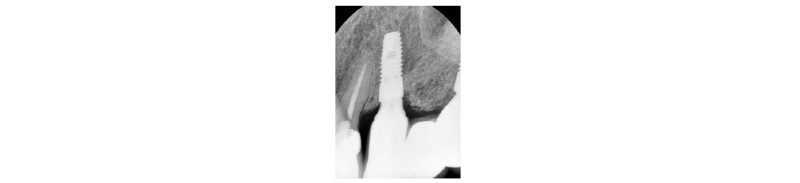

57세의 여성 환자로 기존 브릿지 보철 수복물(#24-27)의 상악 좌측 제 2대구치의 심한 우식으로 인해 내원하여 해당 치아를 발거하였다(Fig. 1). 상악 좌측 제 1 소구치는 근관치료를 시행한 후 보철 수복하기로 하였고 기존 pontic 부위였던 좌측 제 2 소구치와 발거된 제 2 대구치 부위에 #25i, #27i 2개의 임플란트 식립을 통한 브릿지 보철 수복물을 계획하였다(Fig. 2). 기존 pontic으로 유지되었던 좌측 제 2 소구치 부위는 치조제의 심한 수평적 치조골 흡수를 구강 내 임상검사를 통해 확인할 수 있었다. 전층 판막 형성후 상악 좌측 제 2 소구치 부위의 치조정 폭경은 약 2 mm 정도로 측정되었다(Fig. 3, 4). 치조골의 구개측에 약 1 mm의 치조골이 남도록 high speed carbide round bur를 이용하여 치조정에 horizontal intraosseous groove를 형성하였고 협측골의 근심, 원심측에 2개의 vertical intraosseous groove를 형성하였다(Fig. 5). Chisel과 ridge spreader drill (RS kit, Dentium, Korea)을 이용하여 점차적으로 협측 골판을 구개측으로부터 분리시켰다(Fig. 6). Osteotome을 이용, 식립 깊이까지 적용하여 임플란트 식립 부위를 형성하였고 Ø4.3 × 10 mm (Implantium, Dentium, Korea) 임플란트를 식립하였다(Fig. 7). 발치 후 치유된 상악 좌측 제 2 대구치 부위는 상악동 거상술(수직 접근법)을 시행, 골이식을 한 후 4.8 × 10 mm (Implantium, Dentium, Korea)를 식립하였다(Fig. 8). 이후 이종골 이식재(Bio-Oss®, Geistlich, Switzerland)를 식립된 임플란트와 협,구개 측 치조골판 사이의 gap과 협측골판 상방에 적용하고 흡수성 교원질 차폐막(Bio-Gide®, Geistlich, Switzerland)로 피개한 다음 감장절개를 통해 장력없이 봉합하였다(Fig. 9-11). 이후 구강 내 검사 및 방사선 검사를 통해 수술부위 치유상태를 확인하였고 특이한 임상적 소견없이 정상적으로 잘 치유되었다(Fig. 12). 약 3개월 10일 정도의 치유기간 후 이차수술을 시행하였다(Fig. 13). 판막 거상 후 치조제 분할술을 시행하였던 상악 좌측 제 2 소구치 부위에 잘 형성된 신생 골양조직이 관찰되었다(Fig. 14). 상악 좌측 제 2 소구치 부위와 상악 좌측 제 2 구치 부위에 치유지대주를 장착하였고 상악 좌측 제 1 대구치 부위에 추가적으로 임플란트를 1회법으로 식립하였다(Fig. 15). 이차수술 이후 정상적으로 치유가 진행되어 약 2개월 후 최종 보철물 수복을 하였다(Fig. 16, 17). 약 1년 정도의 follow-up시 구강 내 검사와 방사선 검사를 통해서 임플란트 주위 연조직과 변연골이 잘 유지되고 있음을 확인하였다(Fig. 18).

|

Fig. 1. First visit. Panoramic x-ray view. |